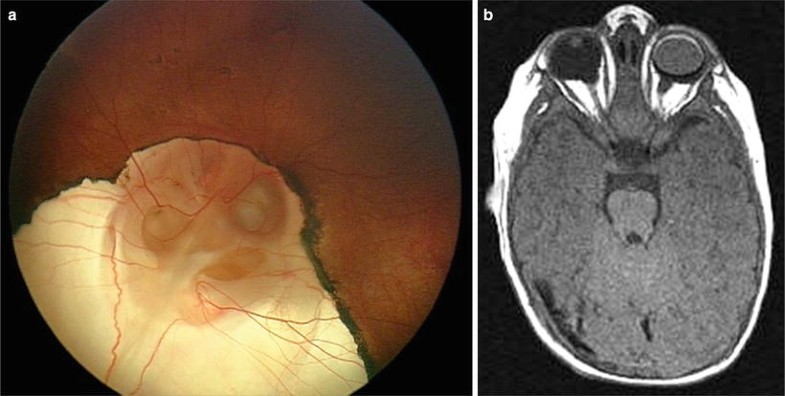

Morning glory disc anomaly with chronic retinal detachment. Top left: Slit lamp photograph of the right eye showing a 10% layered hyphema with sparse multicolored crystals floating within the aqueous. Top right: Slit lamp photograph of the right eye demonstrates multiple, iridescent, needle-like crystals floating freely within the aqueous. Bottom left: Right optic disc photograph demonstrates a morning glory optic disc anomaly. There is a tuft of glial tissue overlying the center of the disc, a slightly elevated yellow annulus surrounding the disc, and a low-lying peripapillary retinal detachment. Bottom right: CT scan showing calcific excavation of the globe at its junction with the optic nerve. (From Brodsky [46, 67], with permission.)